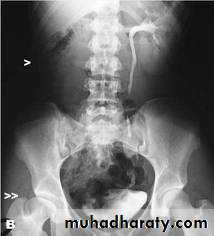

Infantile hydronephrosis ( PUJ OBSTRUCTION ):

IVU shows :

Marked dilatation of pelvis and may be extra-renal.

Calyceal dilatation is late and in advanced cases form foot shape PCS

The ureter is not seen and when it is seen looksnormal .

Delayed film with I.V. diuretic produce gross dilatation .